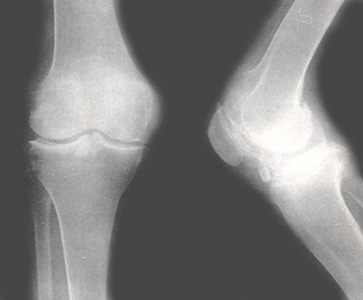

治疗骨质疏松症或关节炎,得视病况而定。他指出,关节炎的多数类型病情并不严重,但给人带来很多烦恼。每天有数百万患者,遭受关节炎或其并发症所带来的疼痛和功能障碍的困扰。医生不只是减轻病人的疼痛而已,而是找出病源,对症下药。市面上有许多强化骨骼的药物,包括预防骨质疏松症与骨折、降低痛风的血尿酸、控制免疫系统避免关节受损等等药物。

钙质补充剂能提供骨骼基本助益,但是骨质疏松症患者必须接受药物治疗。葡萄糖胺(Glucosamine)对已经退化的关节或关节炎症的实际效用并不明显。

他强调,运动对内强化骨骼关节周遭的肌肉有很大帮助,可强健骨骼。如果病人超重,控制体重是关键,以减轻骨关节的负担,尤其是对膝盖的伤害。